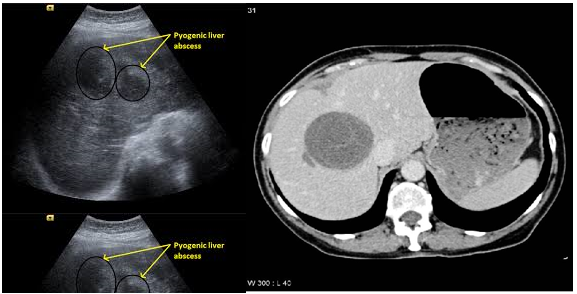

Áp xe gan

Áp xe gan sau TACE có thể do các nguyên nhân: nhiễm khuẩn do viêm đường mật cấp tính, nhiễm khuẩn đường mật mạn tính hoặc nhiễm trùng tĩnh mạch cửa; nhiễm trùng trong quá trình thủ thuật; giảm khả năng miễn dịch do điều trị hóa trị liệu  Các triệu chứng của áp xe gan bao gồm: Hội chứng nhiễm trùng: sốt cao, có thể rét run, bạch cầu tăng, CRP tăng; đau bụng hạ sườn phải. Trên siêu âm, chúng xuất hiện dưới dạng các tổn thương giảm âm không đồng nhất được giới hạn, có thể khó phân biệt áp xe gan với hoại tử khối u hoặc nhồi máu gan ngay sau TACE. Trên hình ảnh cắt lớp vi tính có thể thấy vùng giảm tỷ trọng, giới hạn không rõ cả trước và sau tiêm thuốc cản quang, nhu mô gan xung quanh không thay đổi.

Hình 4: Hình ảnh áp xe gan trên siêu âm (a) và trên cắt lớp vi tính (b)

Chọc hút qua da hoặc đặt sonde dẫn lưu áp xe và sử dụng kháng sinh vẫn là phương pháp điều trị chính. Sử dụng kháng sinh dự phòng trước và sau khi điều trị có thể làm giảm nguy cơ nhiễm trùng sau thuyên tắc